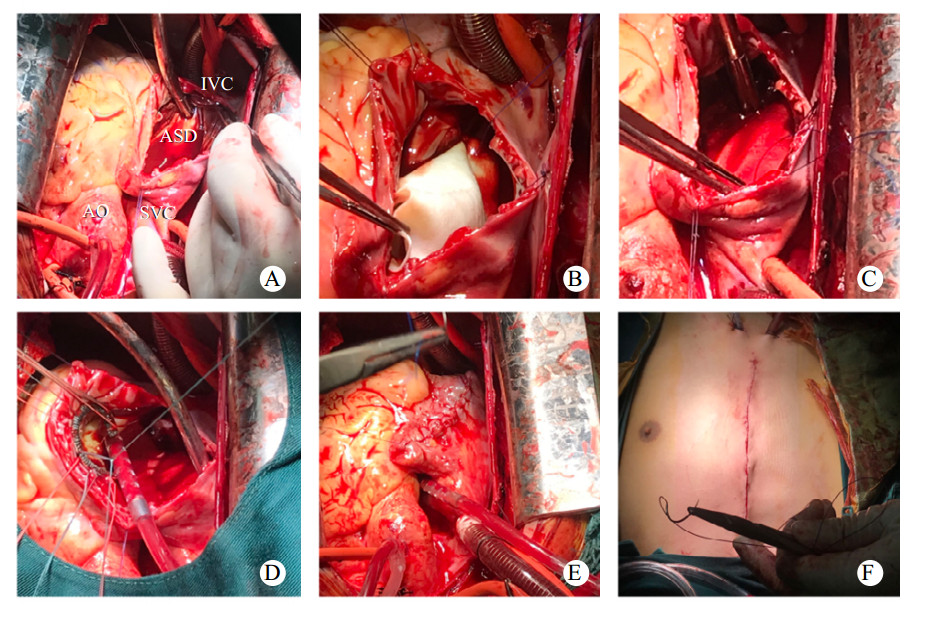

1 资料与方法患者,男性,21岁,于2022年5月18日收治本院,无明显不适主诉,15年前体检时发现ASD,长期门诊随访。患者近期门诊随访时外院心脏超声提示:房间隔缺损(继发孔型),右心增大,肺动脉增宽,轻度肺动脉高压(肺动脉平均压33 mmHg,1 mmHg=0.133 kPa),考虑患者房间隔缺损,存在手术指征,建议手术治疗,门诊以“房间隔缺损”收住入院。入院时查体:神志清楚,体温: 37.2℃,脉搏: 73次/min,血压: 109/66 mmHg,口唇无发绀,可见杵状指,颈静脉无怒张,双肺呼吸音清,未闻及明显干湿啰音,心律不齐,肺动脉瓣听诊区可闻及收缩期杂音,腹软,无压痛及反跳痛,肝脾肋下未及,双侧肾区无明显叩痛,脊柱侧弯,双下肢无水肿,神经系统检查阴性。血气分析氧分压:57 mmHg,血氧饱和度:88.7%,血、尿常规、生化、凝血项无殊。本院经胸心脏超声提示:先天性心脏病, 巨大房间隔缺损合并下腔静脉回流入左房(右向左分流),右心增大,轻度肺动脉高压,估测肺动脉收缩压(pulmonary artery systolic pressure,PASP)40 mmHg(图 1)。胸部高分辨CT平扫提示:心脏饱满,提示肺静脉异常引流,房间隔缺损可能,建议增强(图 2)。术前诊断:先天性心脏病:巨大房间隔缺损(下腔静脉侧及房顶部无房间隔残留组织),轻度肺动脉高压,完全性右束支传导阻滞,脊柱侧弯,胆囊内息肉。根据术前检查,决定进行心脏不停跳房缺修补术(人造补片)以及三尖瓣成形术。全麻后,沿胸骨正中切口开胸,切开右心房,术中所见:右心明显增大,房间隔缺损,下腔静脉无残端,大小约4.0 cm×5.0 cm,三尖瓣瓣环增大,约43 mm, 少量反流,未见肺静脉异位引流、室间隔缺损、动脉导管未闭、下腔静脉异位引流等心内其他畸形。手术体外循环下不停跳牛心包补片修补房缺,三尖瓣成形、置入28# SORIN成形环一枚(图 3)。术程顺利,术后即刻经食道超声未见房间隔明显残余分流,三尖瓣未见明显反流。心电图示窦性心律。术后给与头孢呋辛钠预防感染,护胃、化痰、利尿等对症支持治疗。术后经胸心脏超声提示:房间隔缺损修补术后,房水平未见残余分流,三尖瓣成形术后(图 4)。手术前后左心功能未见明显异常(表 1)。经1周治疗后,患者恢复良好,血气分析氧分压:141 mmHg,血氧饱和度:99.9%,予带药出院。

| A: 术中暴露巨大房缺,下腔静脉无残端,右下肺静脉呈树枝状回流入心房; B: 放入牛心包补片; C: 补片缝合; D: 三尖瓣成形; E: 缝合右心房; F: 关胸。AO: 主动脉;SVC: 上腔静脉;ASD:房间隔缺损;IVC:下腔静脉 图 3 患者手术过程 |